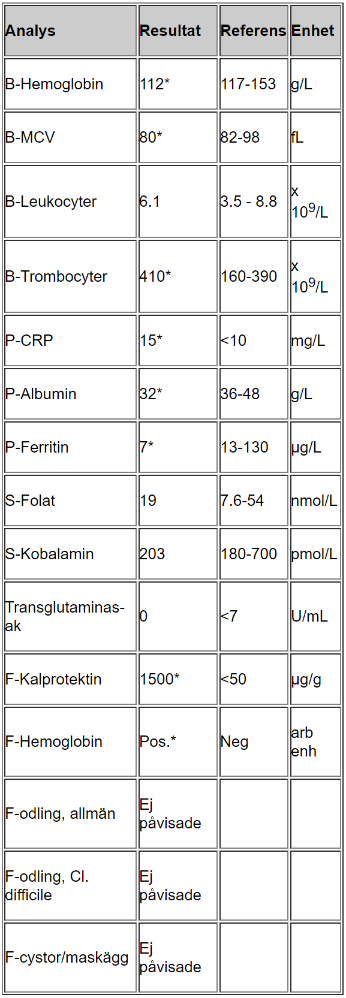

Tolka proverna

- B-hemoglobin, MCV, ferritin lågt vilket tyder på inflammation/blödning, eventuellt problem med näringsupptag

- Trombocyter högt som kompensation för blödning

- CRP lite högt tyder på låggradig inflammation

- Albumin lågt kan tyda på inflammation (omvänd markör)

- F-Kalprotektin högt tyder på IBD

- F-hemoglobin tyder på att det pågår blödning i tarmen, hon har inte uppmärksammat det själv vilket tyder på blödning något mer proximalt i tarmen